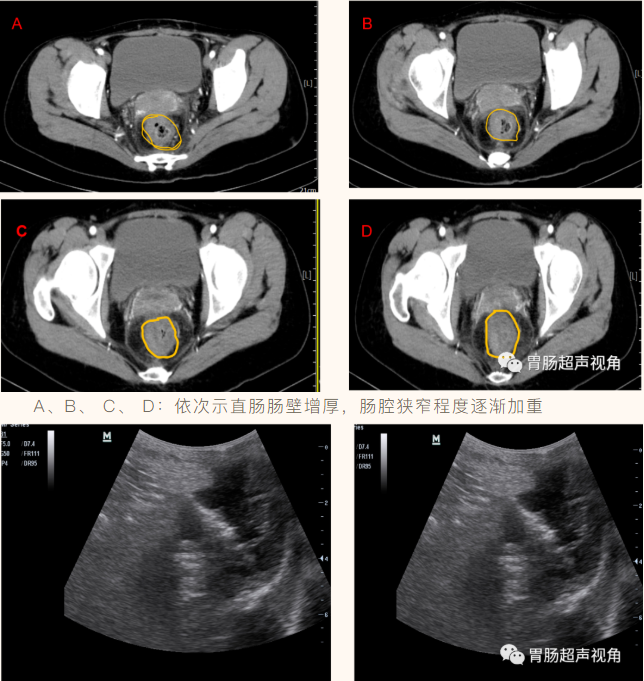

• CT示:

子宫颈后缘见团片状低密度影,增强扫描呈弱强化,直肠后壁及右侧壁局灶性增厚。

• 直肠灌入300ml造影剂经腹探查:直肠肠腔重度狭窄,仅见液体呈线状迂曲缓慢进入。

• 直肠肠壁可见多发低回声结节向腔内隆起,较大着位于直肠后壁,大小约5.2x3.3x2.0cm(长x宽x厚),前壁另可见片状不规则增厚,较厚处约1.1cm,累及长度约4.0cm(环绕肠壁约1/2周),肠粘膜面可见一较大凹陷,长约2.2cm,深约0.7cm,粘膜凹陷处可见强回声附着。